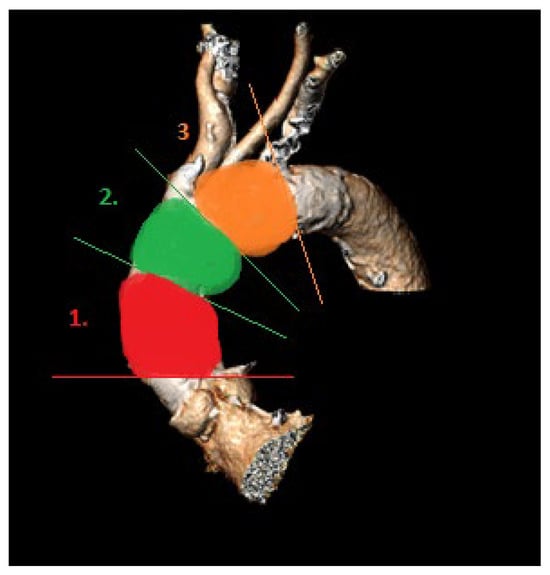

- (1)

- Proximal segment, from sinotubular junction to mid-ascending aorta (at level of pulmonary artery bifurcation);

- (2)

- Middle segment, from mid-ascending aorta (at pulmonary artery bifurcation) to origin of brachiocephalic trunk;

- (3)

- Distal segment, from origin of brachiocephalic trunk to origin of left subclavian artery.